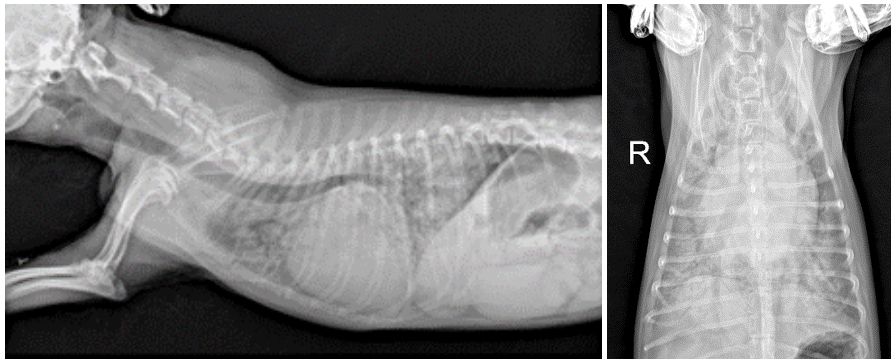

방사선 촬영 결과,

VHS (Vertebral Heart Score)는 12.3, VLAS (Vertebral Left Atrial Size)는 3.0으로 확인되었습니다.

흉부 방사선 촬영상 심장은 정상보다 매우 커져 있었으며, 특히 좌심방이 확장되어 있는 상태임을 의미합니다.

또한 폐 전체에 걸쳐 심한 간질–폐포 패턴이 확인되었는데, 이는 폐에 액체가 차 있는 폐부종(CPE, cardiogenic pulmonary edema) 의

전형적인 방사선 소견입니다.

아이의 경우 심장 기능 저하로 인해 폐에 물이 차면서 숨 쉬는 것이 매우 어려운 상태였고, 이로 인해 위급한 호흡곤란이 발생한 것으로 판단되었습니다. ▼